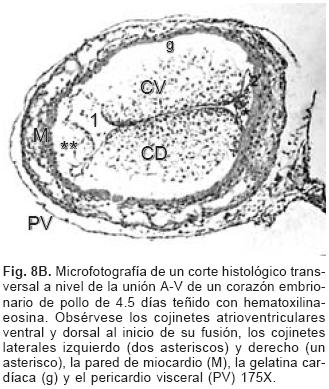

El proceso embrionario de la tabicación A–V se establece con el crecimiento y desarrollo del mesénquima cardíaco de las almohadillas endocárdicas dorsal y ventral del canal A–V que en el embrión ocurre entre los estadios (25 al 29) de Hamburguer y Hamilton17,18 (Fig. 8A), dichas almohadillas completamente desarrolladas se fusionan y conforman el tabique A–V que divide al canal A–V común en dos: derecho e izquierdo (Fig. 8B) en cuyas paredes se diferencian dos anillos fibrosos situados a desnivel, uno para la válvula tricúspide y otro para la válvula mitral (Fig. 9A). El extremo craneal de este tabique se dobla hacia la izquierda, crece dentro del canal A–V izquierdo y se transforma en el esbozo de la porción central de la valva medial (aórtica) de la válvula mitral21 (Fig. 9B), proceso que ocurre en los embriones humanos en los horizontes de Streeter del XIII al XVI.19,20 El espacio comprendido entre el tabique ventricular y la valva medial de la válvula mitral constituye el tracto de salida del ventrículo izquierdo. La valva lateral de la válvula mitral se separa como un faldón de la pared del canal A–V y del ventrículo izquierdo del que se diferencian también sus cuerdas tendinosas y músculos papilares (Fig. 9B). La válvula tricúspide se desarrolla por el mismo proceso de delaminación para conformar tres láminas de miocardio que corresponden a las valvas septal, anterior y posterior con sus respectivas cuerdas tendinosas y músculos papilares.1